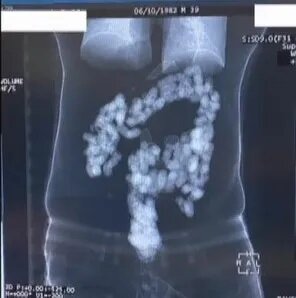

Mədələrindən 2 kilo heroin çıxdı - VİDEO

Mədəsində 2 kiloqram heroin keçirmək istəyənlər saxlanılıb.

Həbs olunan R.Y. və H.F. adlı şəxslər mədəsində 244 kapsulda 2 kiloqram heroin keçirtmək istəyiblər.